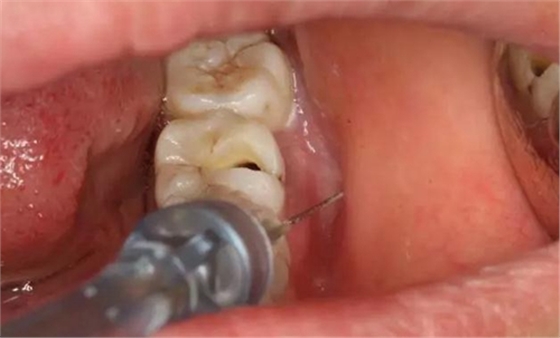

圖4.行下頜無痛阻滯麻醉。

圖5.加局部浸潤麻醉。